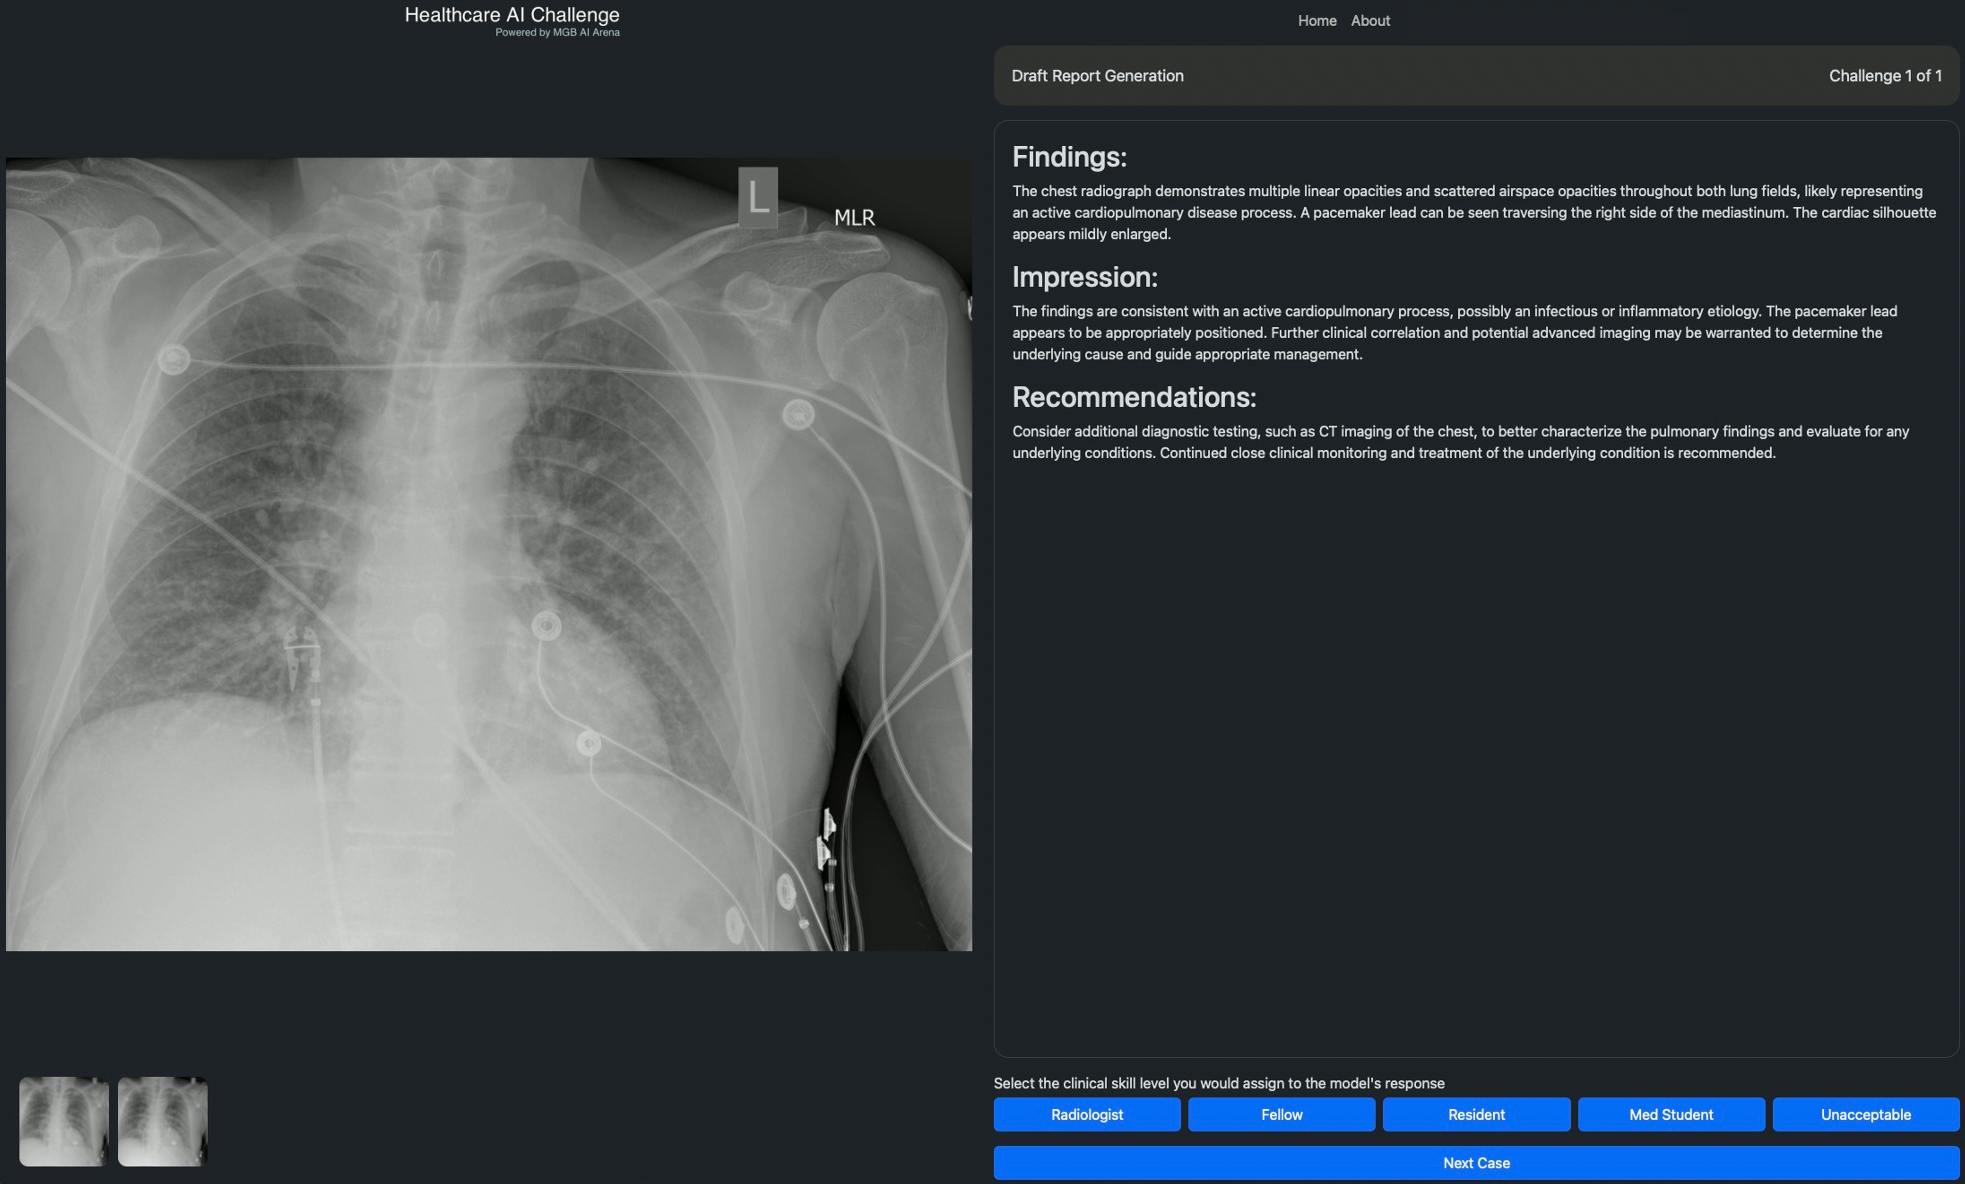

Participating healthcare professionals will be granted access to the Healthcare AI Challenge that features new AI solutions they can assess for effectiveness on specific medical tasks, such as providing medical image interpretation, in a simulated environment. Participants with relevant healthcare credentials can then provide their feedback on the solutions’ performance and utility, which will generate publicly available insights and analytics. By crowdsourcing input from healthcare professionals, the Healthcare AI Challenge seeks to create continuous, consistent and reliable expert evaluations of AI solutions in medicine. Importantly, scaling the evaluation of these technologies and sharing the insights broadly and transparently can result in societal benefit for healthcare stakeholders and patients globally.

Healthcare professionals at institutions that are a part of the Healthcare AI Challenge Collaborative who register can log onto the Healthcare AI Challenge, select one of several events—such as image interpretation—and choose from a series of challenges to assess any one of the multiple foundation models available on the platform. The image interpretation challenges include questions focused on draft report generation, key findings, differential diagnosis, among others. The expert then rates the clinical skill level of the foundation models’ responses, which contributes to the insights and analytics rankings. Only verified healthcare professionals can participate in challenges that contribute to the rankings. The results of the Healthcare AI Challenge can be followed by the general public at HealthcareAIChallenge.org.